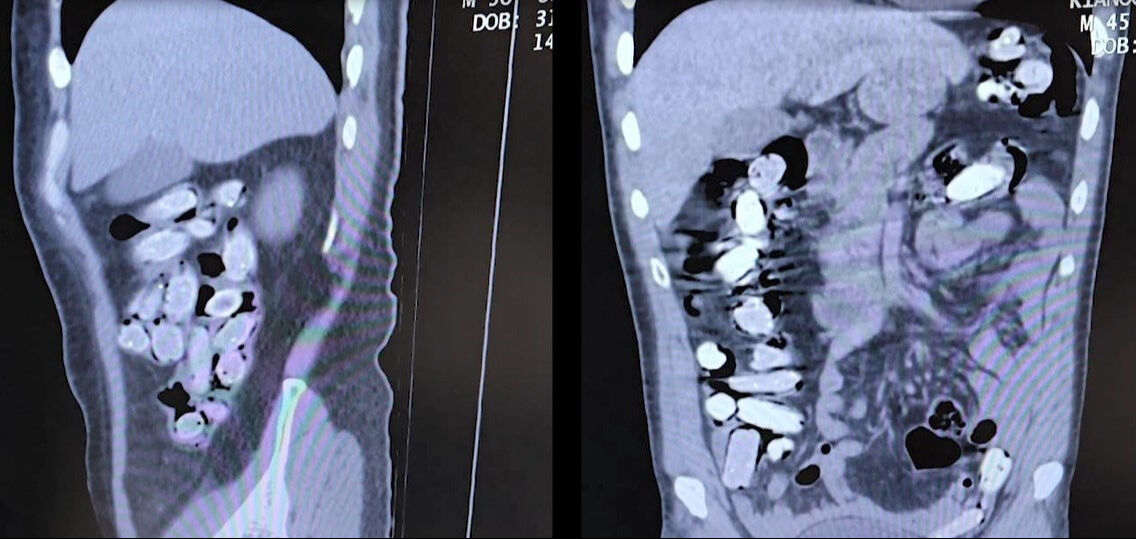

Gözaltına alınan ve Tatvan Devlet Hastanesine sevk edilen şüphelilerin röntgen ve tomografi görüntülerinde mide ile bağırsaklarında çok sayıda yabancı cisim bulunduğu tespit edildi.

Yapılan tıbbi müdahale ile şüphelilerin paketleyerek yuttuğu toplam 96 adet daralı ağırlığı 1 kilo 340 gram Afyon sakızına el konuldu. Şüpheliler, çıkarıldığı adli mercilerce tutuklanarak cezaevine gönderildi.